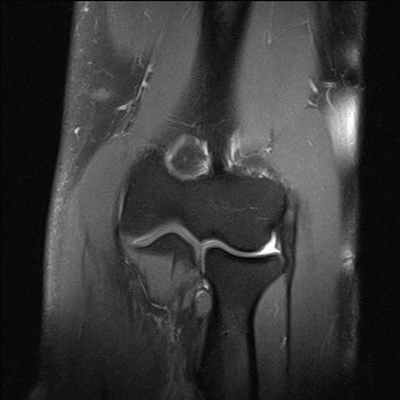

(Левый) При рентгенографии голеностопного сустава в передне-задней проекции определяются признаки медиальной нестабильности: отсутствие конгруэнтности суставных поверхностей и вальгусная деформация. Причиной нестабильности стал артродез подтаранного сустава. Выявляются признаки вторичного остеоартроза.

(Правый) При рентгенографии голеностопного сустава в передне-задней проекции визуализируются признаки остеоартроза, возникшего в результате долговременного сохранения нестабильности сустава после разрыва синдесмоза. В области повреждения межкостной связки отмечается увеличение расстояния между большеберцовой и малоберцовой костями и наличие периостальной реакции. (Левый) При рентгенографии голеностопного сустава в проекции суставной щели определяются признаки длительной латеральной нестабильности сустава вследствие разрыва латеральных коллатеральных связок. Отмечаются отсутствие конгруэнтности суставных поверхностей голеностопного сустава, его варусная деформация, проявления вторичного остеоартроза.

(Правый) Пациент, длительно страдающий нестабильностью голеностопного и подтаранного суставов. При МРТ в коронарной плоскости на Т2ВИ в режиме FS визуализируются давние разрывы множества связок. ПМС и задняя таранно-малоберцовая связка частично восстановились, однако некоторая их растянутость и неровный контур сохраняются. Также наблюдается разрыв задней нижней межберцовой связки. (Левый) Пациент, длительно страдающий нестабильностью голеностопного сустава. При МРТ в коронарной плоскости на Т2ВИ в режиме FS определяются разрывы ПМС и глубокого слоя дельтовидной связки. Также в области купола таранной кости выявляется уменьшение толщины суставного хрящам.